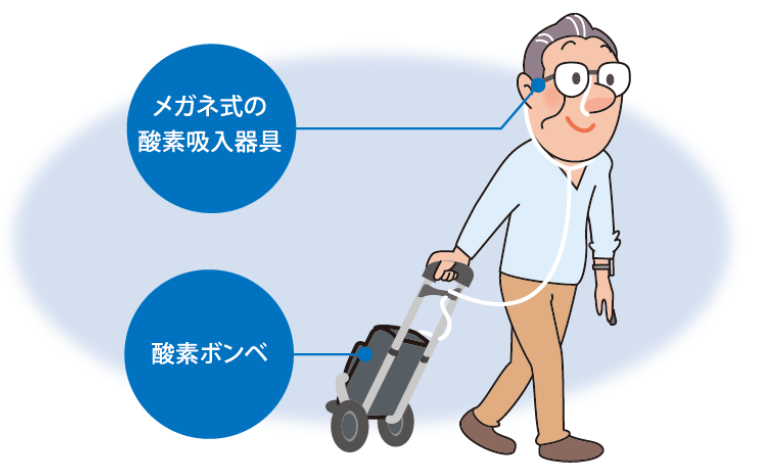

在宅酸素療法 HOT。

在宅酸素療法 HOT。

在宅酸素療法 HOT。

知っておきたい 在宅酸素療法の注意点や費用 - LIFULL 介護 ライフル介護。

在宅酸素療法 HOT。

酸素を吸いながら生活しやすい環境をつくる医療トピックス48号WEB版すこやかライフぜん息などの情報館大気環境・ぜん息などの情報館独立行政法人環境再生保全機構。

在宅酸素療法 HOT。